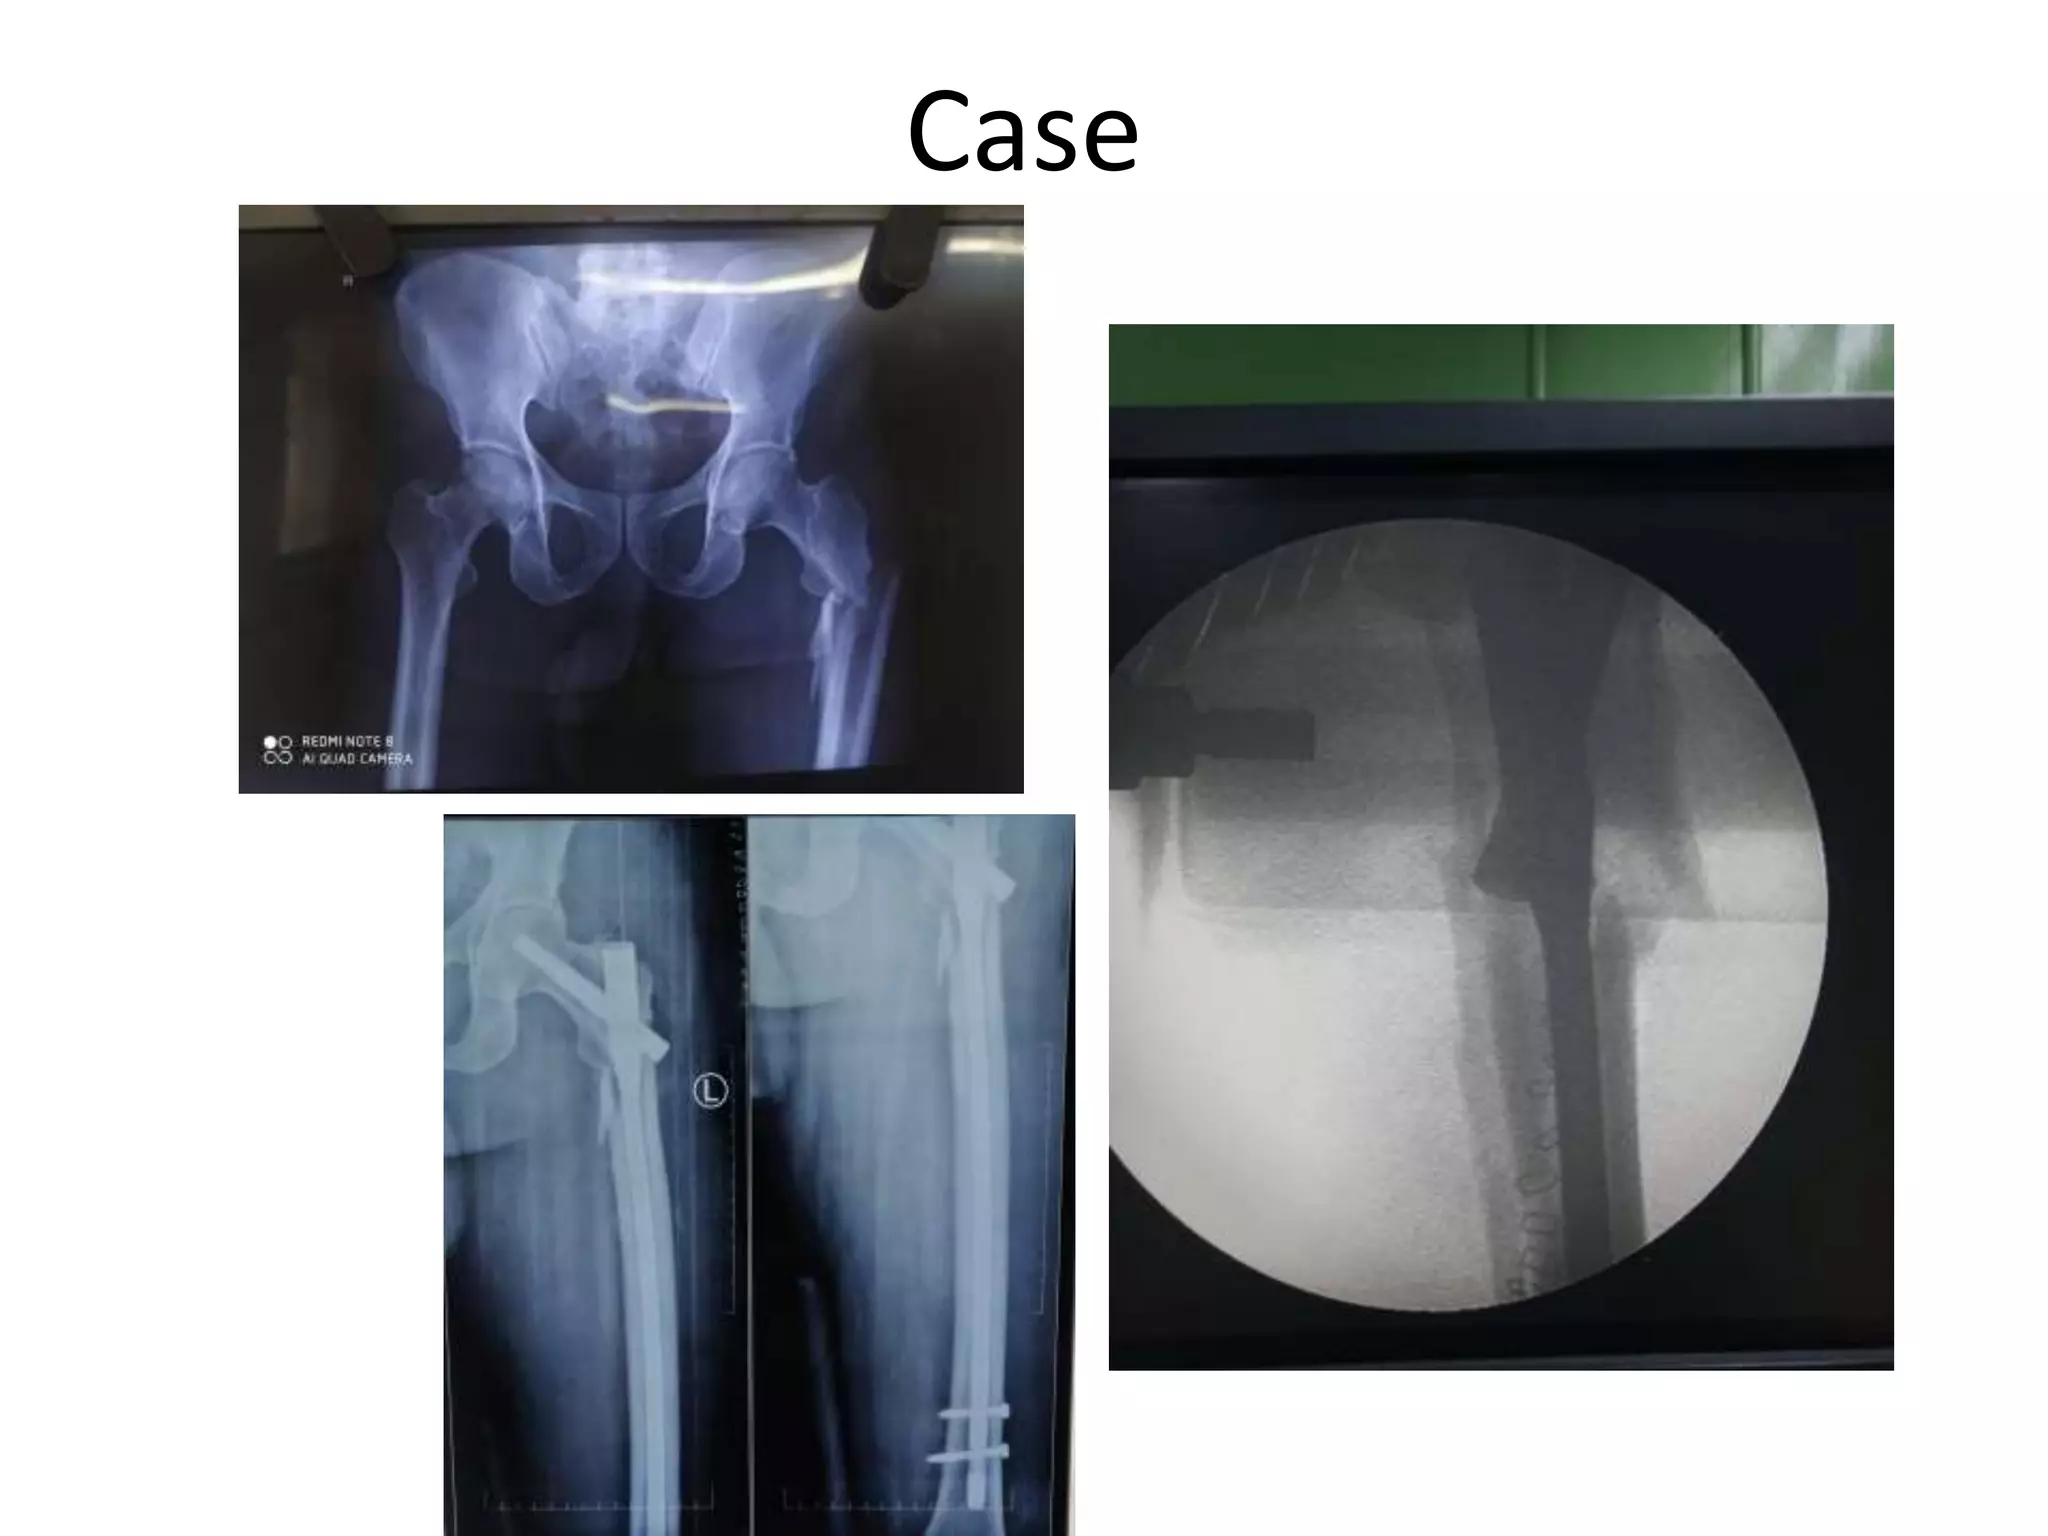

Case

50Year old male .H/O RTA. Otherwise fit.

Case 50Year old male.H/O RTA. Otherwise fit.